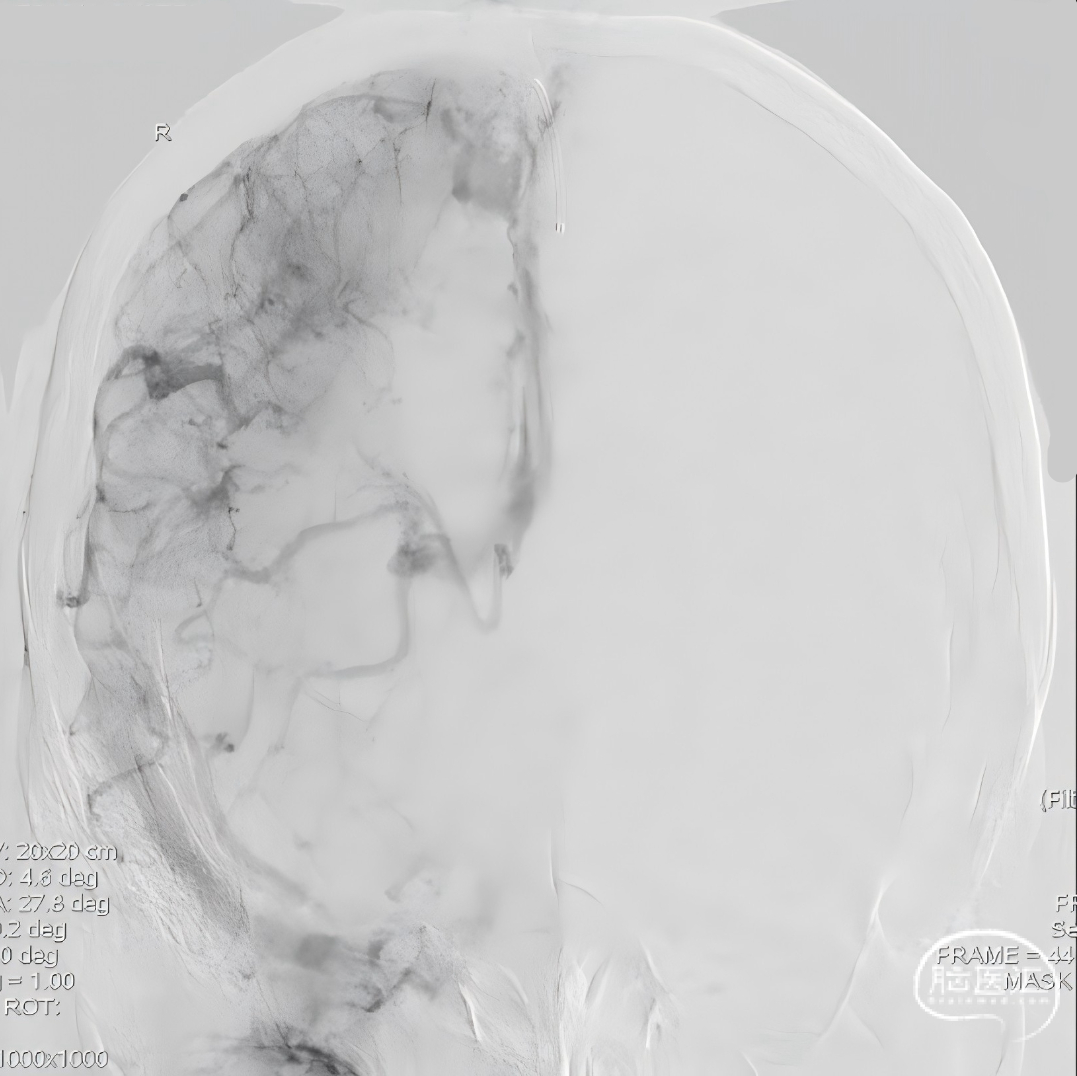

经中间管手推造影,确认血栓位置。

反复抽吸,多次中间管于负压状态下无回血时,负压状态撤出体外,可见大量血栓。

单纯抽吸难以实现良好再通,经300cm微导丝长交换送入115cm Navien™颅内支撑导管;选用5*30mm球囊扩张,碎栓。

球扩后造影,上矢状窦接触溶栓尿激酶20万U。

球囊扩张和接触溶栓后,再次经中间管反复抽吸后复查造影。

再次给予尿激酶10万U后复查造影。